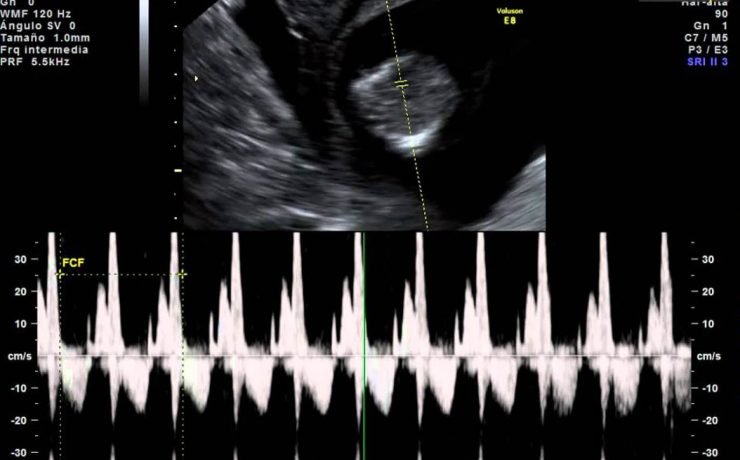

La vesícula biliar se divide en fundus, cuerpo y cuello, en el cuello puede haber un infundíbulo o “Bolsa de Hartmann” Puede haber falta de visualización por: Colecistectomía previa Contracción fisiológica Conducto de vesícula biliar fibrosado: colecistitis crónica Vesícula biliar llena de aire o colecistitis enfisematosa Agenesia Localización ectópica PATOLOGIA